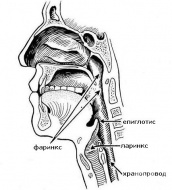

S11.2 Открита рана, обхващаща фаринкса и шийната част на хранопровода

Открита рана, обхващаща фаринкса и шийната част на хранопровода са рядкост. Епидемиологични проучван...